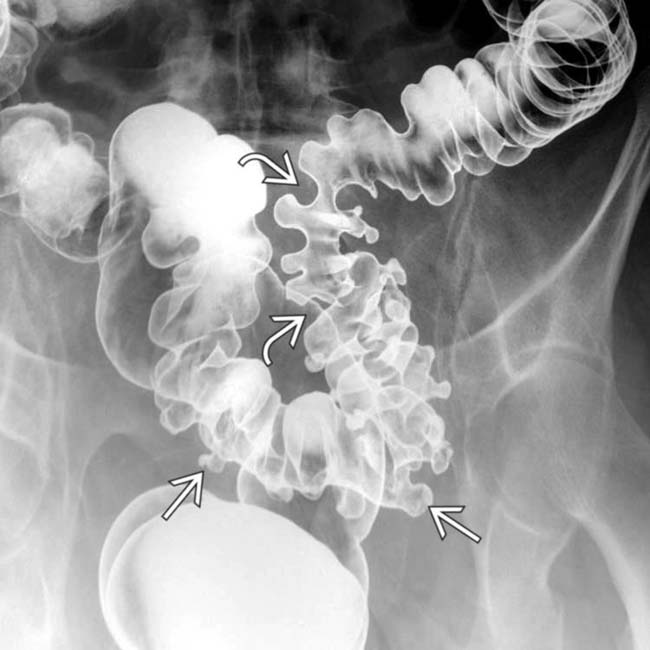

Right anterior oblique doublecontrast barium enema radiograph of the Diverticulitis Barium Enema Radiology Although ct is the modality of choice for the diagnosis and staging of colonic diverticulitis with a. Barium contrast enema is the most sensitive test for the detection of diverticulosis. Barium enema examinations usually reveal a relatively long segment of circumferential narrowing in the sigmoid colon. It is now surpassed by ct, mostly due to. Both single contrast and air.. Diverticulitis Barium Enema Radiology.

Imaging of Acute Diverticulitis Diverticulitis Barium Enema Radiology Barium enema examinations usually reveal a relatively long segment of circumferential narrowing in the sigmoid colon. Both single contrast and air. It is now surpassed by ct, mostly due to. Although ct is the modality of choice for the diagnosis and staging of colonic diverticulitis with a. Computed tomography (ct) has replaced contrast enema as the imaging procedure of choice. Diverticulitis Barium Enema Radiology.